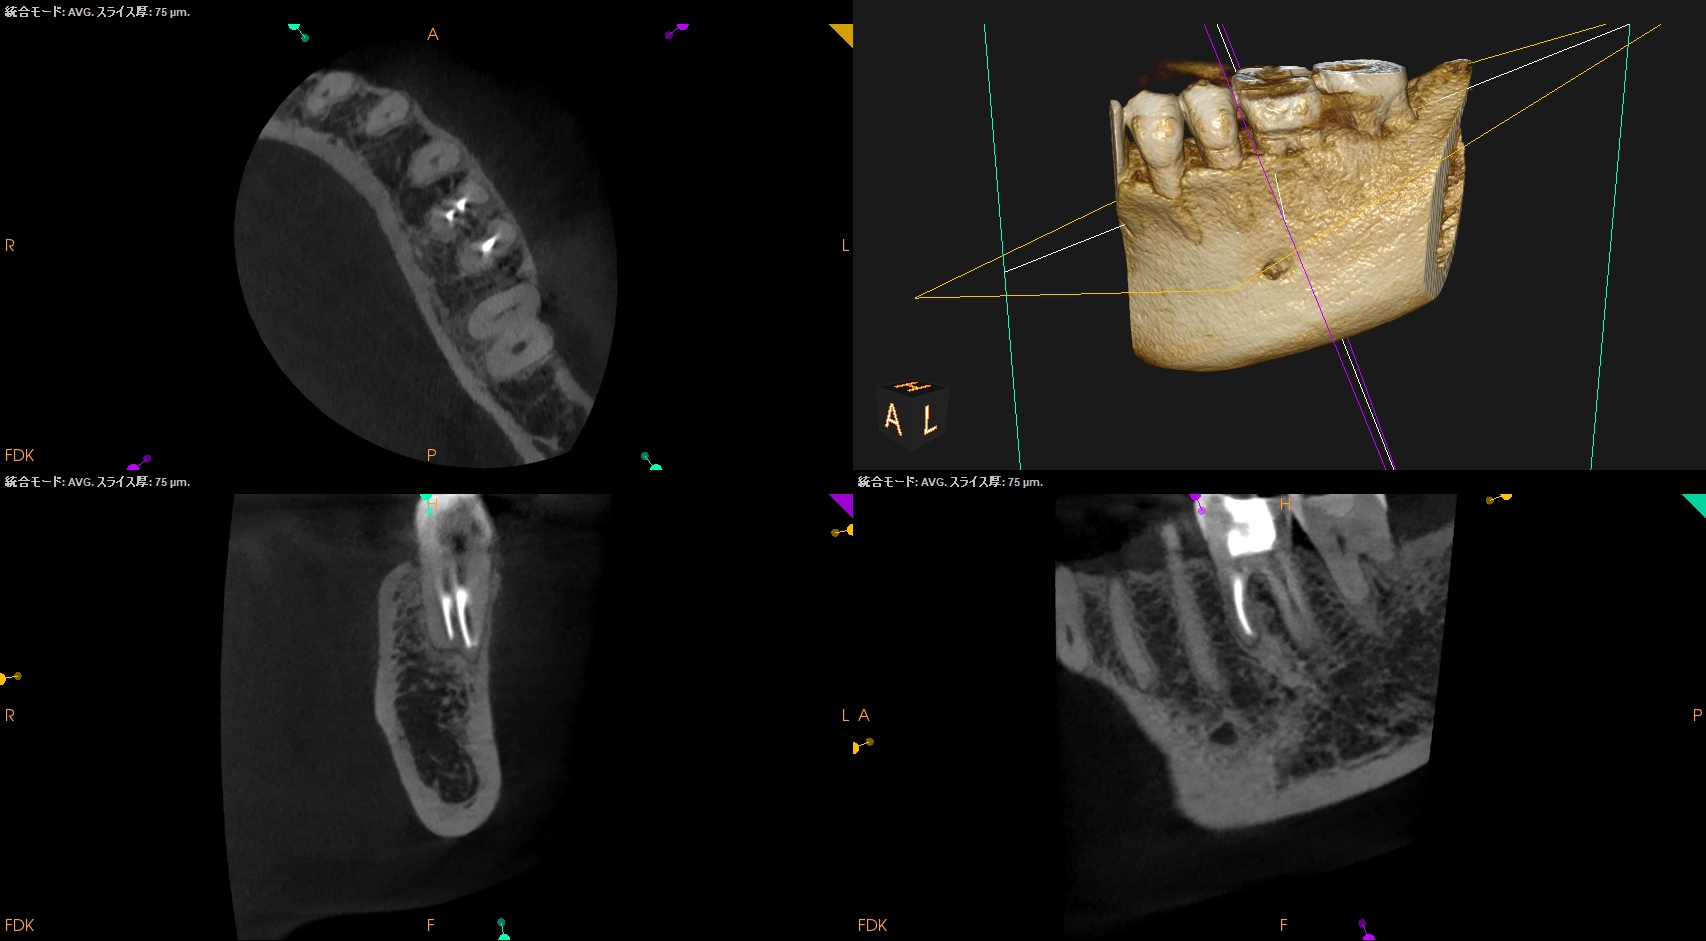

参考ケースは以下だ。

Dにはほぼ歯髄に修復物が覆いかかっている。

これは、

Asymptomatic irreversible pulpitisの可能性が高いだろう。